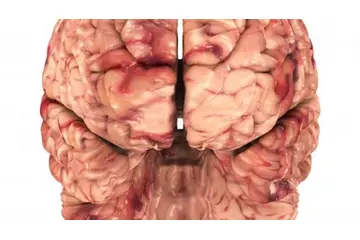

Beyin Dokusunun Sağlık Üzerindeki Etkileri Beyin dokusunun sağlıklı bir şekilde işlev görmesi, genel sağlık üzerinde büyük etkiye sahiptir. Beyin dokusundaki hasar veya bozulmalar, birçok nörolojik hastalığın temelini oluşturur. Öne çıkan sağlık sorunları arasında:

Sonuç Beyin dokusu, insan vücudundaki en karmaşık ve kritik yapılar arasında yer almaktadır. Gri ve beyaz madde, beyin işlevselliğini etkileyen temel bileşenlerdir. Bu dokuların sağlığının korunması, bireylerin bilişsel ve fiziksel sağlığı açısından büyük önem taşımaktadır. Bilimsel araştırmalar ve tıbbi gelişmeler, beyin dokusunun özelliklerini anlamak ve olası hastalıkların tedavi yöntemlerini geliştirmek için devam etmektedir. |